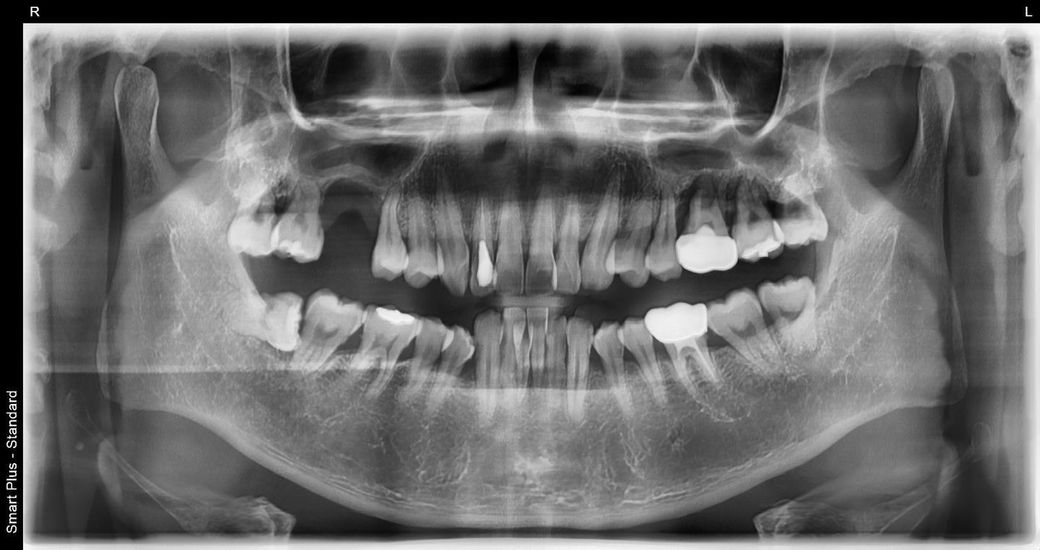

어금니 치료 임플란트, 브릿지 고민 도와주세요

치과 여러군데 견적을 받았습니다. 전문가분들의 최종 의견이 궁금하네요

일단 브릿지, 임플란트는 제가 선택을 해야 하는거라 고민입니다.

왼쪽 임플란트 2개, 브릿지 1개 진행, 오른쪽 임플란트 1개 또는 브릿지로 진행 (선택사항)

왼쪽 임플란트 3개, 오른쪽 임플란트3개 (갯수는 선택사항)

고민되는 부분은 브릿지를 할경우 이미 양쪽 잇몸뼈가 많이 없는 상태인데 얼마 못쓰고 결국엔 임플란트를

해야할거 같고 한번에 또 6개를 다 하자니 비용도 크고 고민스럽네요.. 전문가분들이 보시기엔 어떤가요?

일단, 전반적으로 잇몸뼈 흡수가 심해서 임플란트를 하고자 하는 경우 상악동과 관련하여 거상술, 뼈이식술이 필수적으로 필요한 케이스입니다.

브릿지를 하고자 하는 경우 브릿지의 기둥이 되는 양쪽 치아가 건전해야 하는데 그리 상태가 좋진 못해보입니다.

잇몸뼈가 많이 안좋은 상태인거 같습니다. 시간적 여유가 되신다면 뼈이식을 하고 나서 기다렷다가 임플란트를 하시고 시간이 안되면 한쪽이라도 브릿지 치료를 먼저 하시는게 좋을것같습니다.